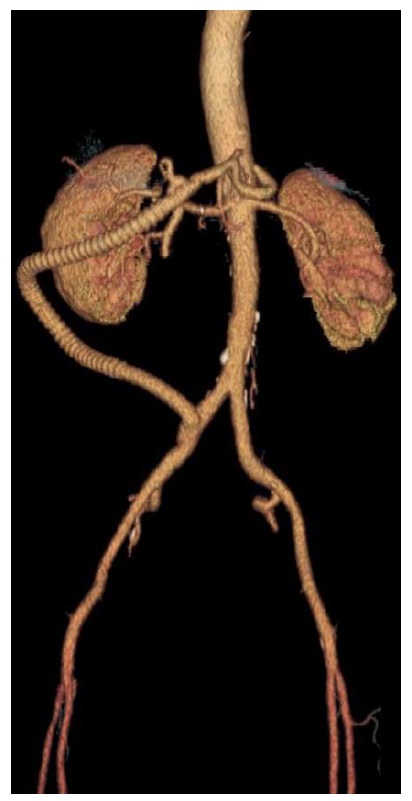

She underwent an iliohepatic bypass with an 8mm PTFE graft (figure 2). Postoperatively, there was a suspicion of vascular prosthesis infection; however, the patient fully recovered under antibiotic treatment. She was discharged after 51 postoperatively days. A study of prothrombotic factors was performed only with the JAK2 V617F mutation being identified.